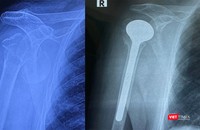

Bệnh viện Việt Đức thay khớp vai thành công cho bệnh nhân cao tuổi nhất Việt Nam